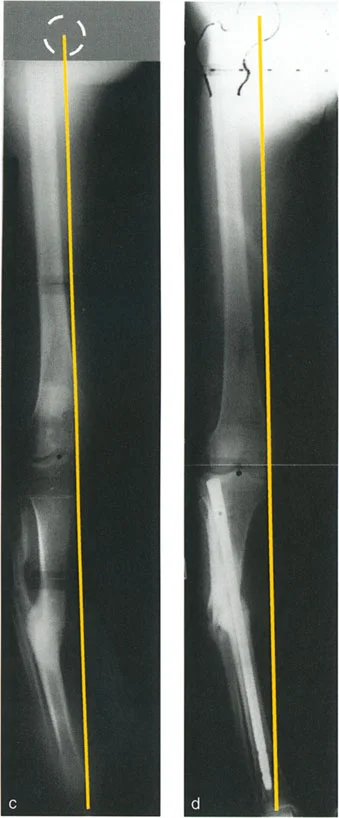

2. التصوير الشعاعي المتقدم:

تُعد الأشعة السينية هي الأداة الأساسية لتشخيص هذه التشوهات، ولكنها تتطلب تقنيات خاصة:

الأشعة السينية الكاملة للطرف (Full-Length Standing X-rays):

- يتم التقاط هذه الأشعة للمريض وهو واقف لتحمل الوزن، وتشمل العظم المصاب بالكامل بالإضافة إلى المفصلين أعلاه وأسفله (مثل الورك والركبة والكاحل للساق).

- تُؤخذ هذه الأشعة في وضعين رئيسيين: الأمامي الخلفي (AP) والجانبي (Lateral).

- أهميتها: تسمح هذه الصور للدكتور هطيف بتقييم المحور الميكانيكي للطرف بالكامل وتحديد مدى انحرافه، وقياس زوايا الانحراف وحجم الانزياح بدقة.

- يوفر صورًا ثلاثية الأبعاد (3D) للعظم، وهو أمر بالغ الأهمية لتحديد طبيعة التشوه في جميع المستويات، خاصة في حالات التشوهات المعقدة التي قد لا تظهر بوضوح في الأشعة السينية ثنائية الأبعاد.

- أهميتها: يساعد في تحديد مواقع الكسور السابقة، وتقدير حجم الانزياح الدوراني (التواء العظم)، وتحديد كثافة العظم، وهو أمر حيوي للتخطيط الجراحي.